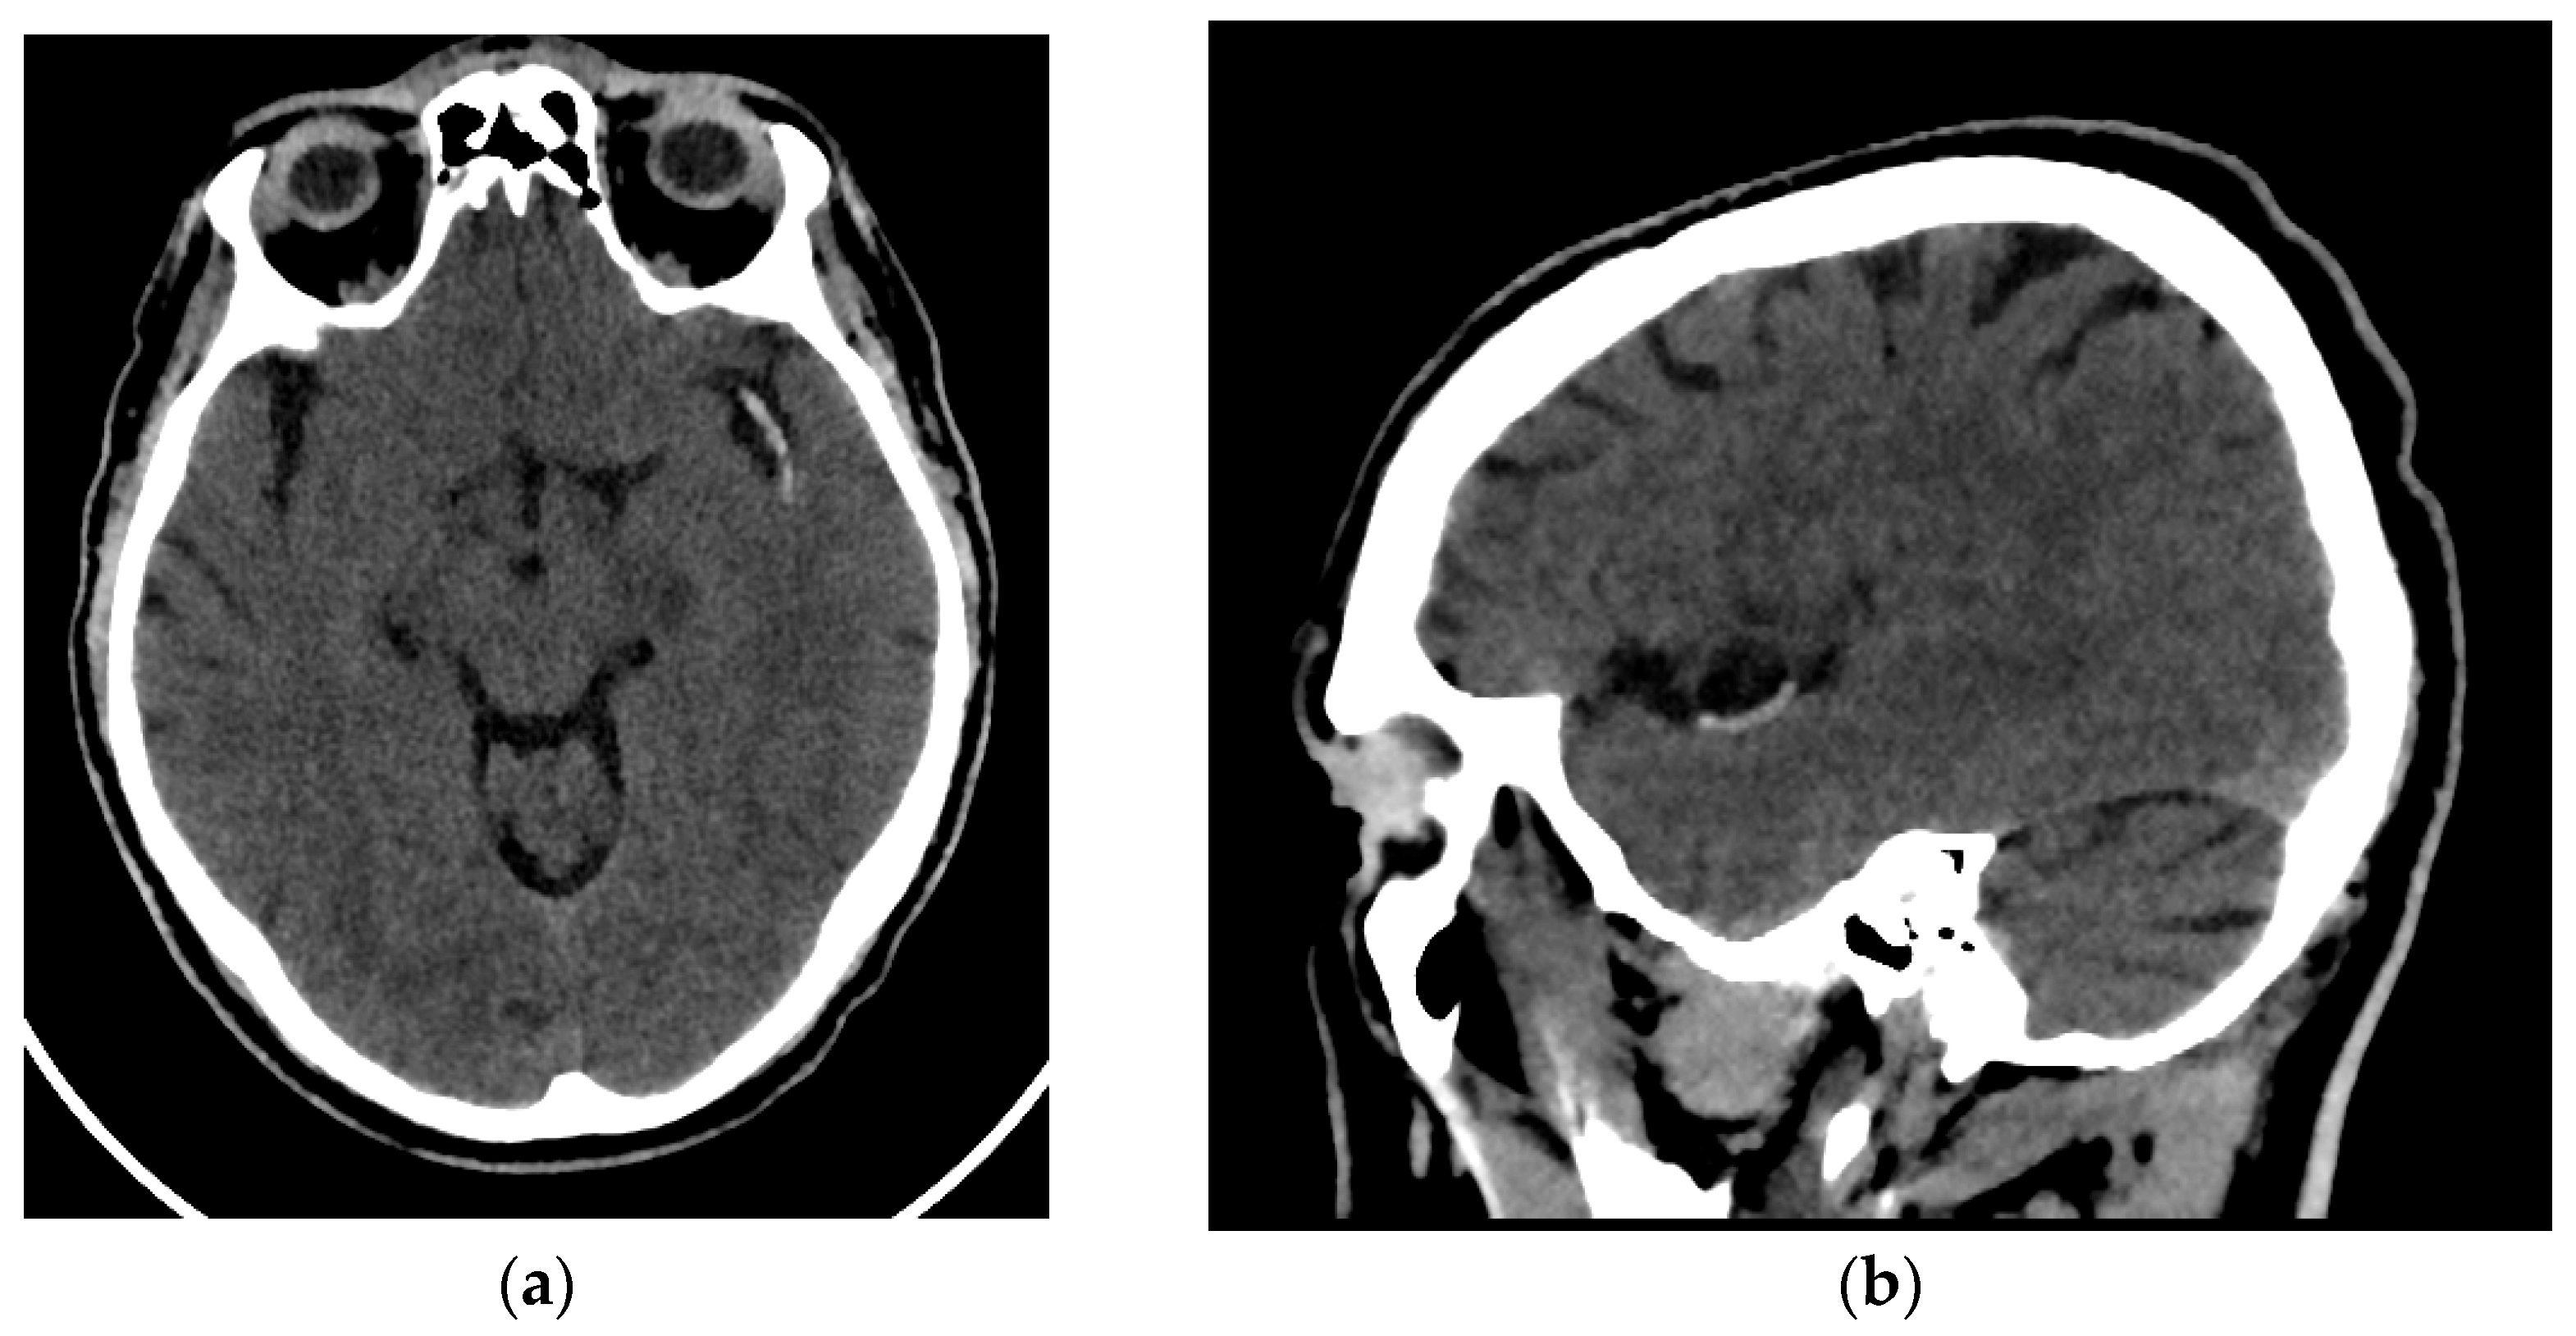

All patients enrolled in the study underwent an NCCT at our hospital utilizing one of two different CT scanners (16 rows of detectors, 120 kV) of the same make and model (Phillips Ingenuity; Amsterdam, The Netherlands) during the diagnosis process of AIS. Patients were randomly assigned to each scanner. The images obtained had a slice thickness of 0.625 mm. Although reconstructions with a thickness of 1 mm were available, they were not used for analysis. The window width and center were set at 80 and 40 Hounsfield units, respectively (Figure 1).

Figure 1. Brain NCCT of a patient with AIS and the hyperdense MCA sign. This is one of the radiological signs of AIS in NCCT. (a) Axial NCCT scan of a patient with a hyperdense left MCA sign. (b) Sagittal NCCT scan of the same patient.